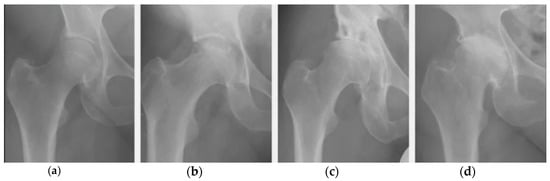

- Kraus, V.B.; Kilfoil, M.; Hash, T.W.; McDaniel, G.; Renner, J.B.; Carrino, J.A.; Adams, S. Atlas of radiographic features of osteoarthritis of the ankle and hindfoot. Osteoarthritis Cartilage 2015, 14, 2059–2085. [Google Scholar] [CrossRef]

- Knee Osteoarthritis: Forms, Diseases, Primary Analyzes, Stages. Available online: https://gp195.ru/bolezni/osteoartrit-lechenie.html (accessed on 15 December 2020).